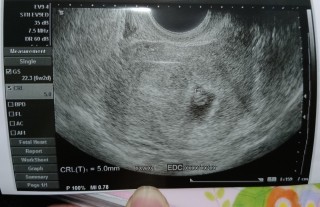

GS22.3mm CRL5.0mm 前回は心拍確認前の稽留流産で今回の内診もドキドキで受けましたが、チカチカと光るエコーをみて涙目でした。次は二週間後!成長してる我が子をこの目でみたいです!